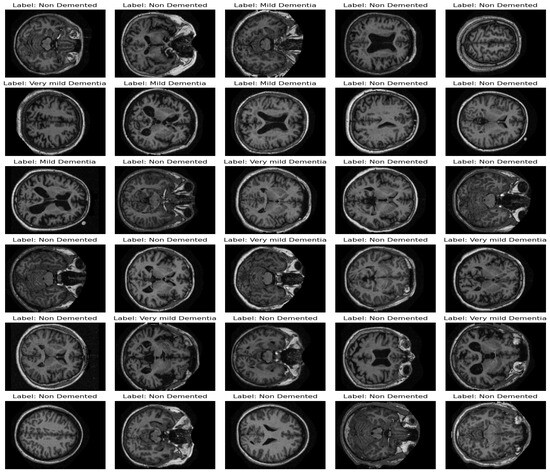

3.1. Dataset and Data Pre-Processing

Data Preparation and Handling Class Imbalance